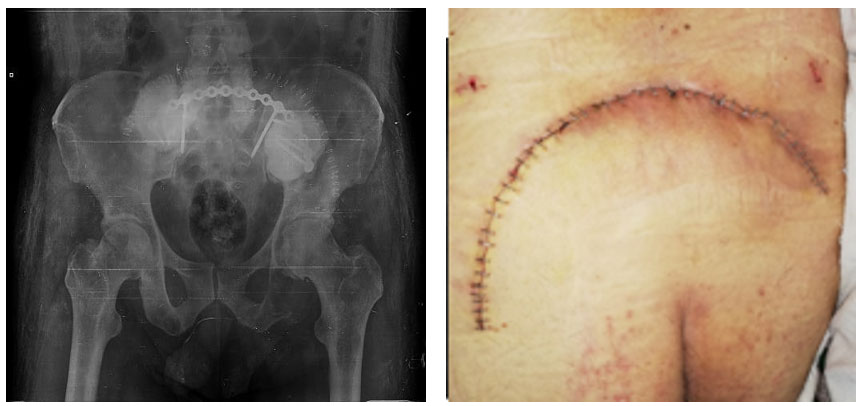

Görsel Açıklamaları

Ameliyat esnası: Tümörün temizlendikten sonra oluşan boşluğun kemik çimentosu ile doldurulması ve titanyum plak ile güçlendirilmesi görülmekte

Ameliyat sonrası: Tümörün temizlendikten sonra oluşan boşluğun kemik çimentosu ile doldurulması ve titanyum plak ile güçlendirilmesi ve yara iyileşmesi görülmekte